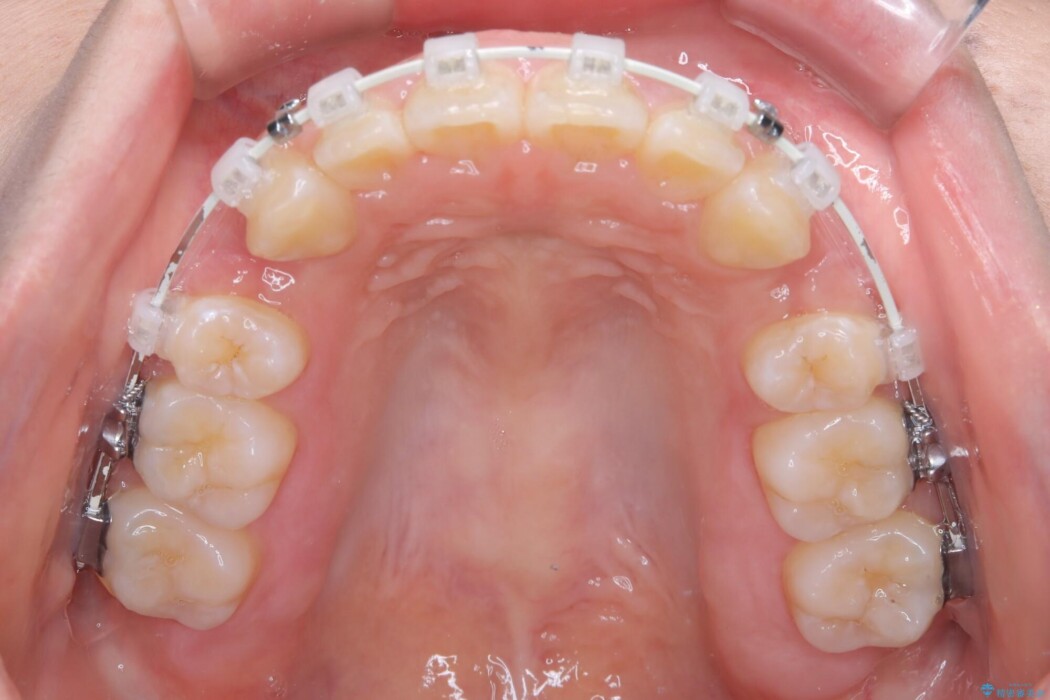

矯正検査の結果、前歯が外側に強く倒れ込んでいる「唇側傾斜(しんそくけいしゃ)」が認められ、口元の突出感の原因になっていました。

この傾斜を根本から正し、前歯を十分に後方へ下げるスペースを確保するため、上下左右の4番を抜歯し、目立ちにくい審美ワイヤー装置にて治療を行うこととしました。